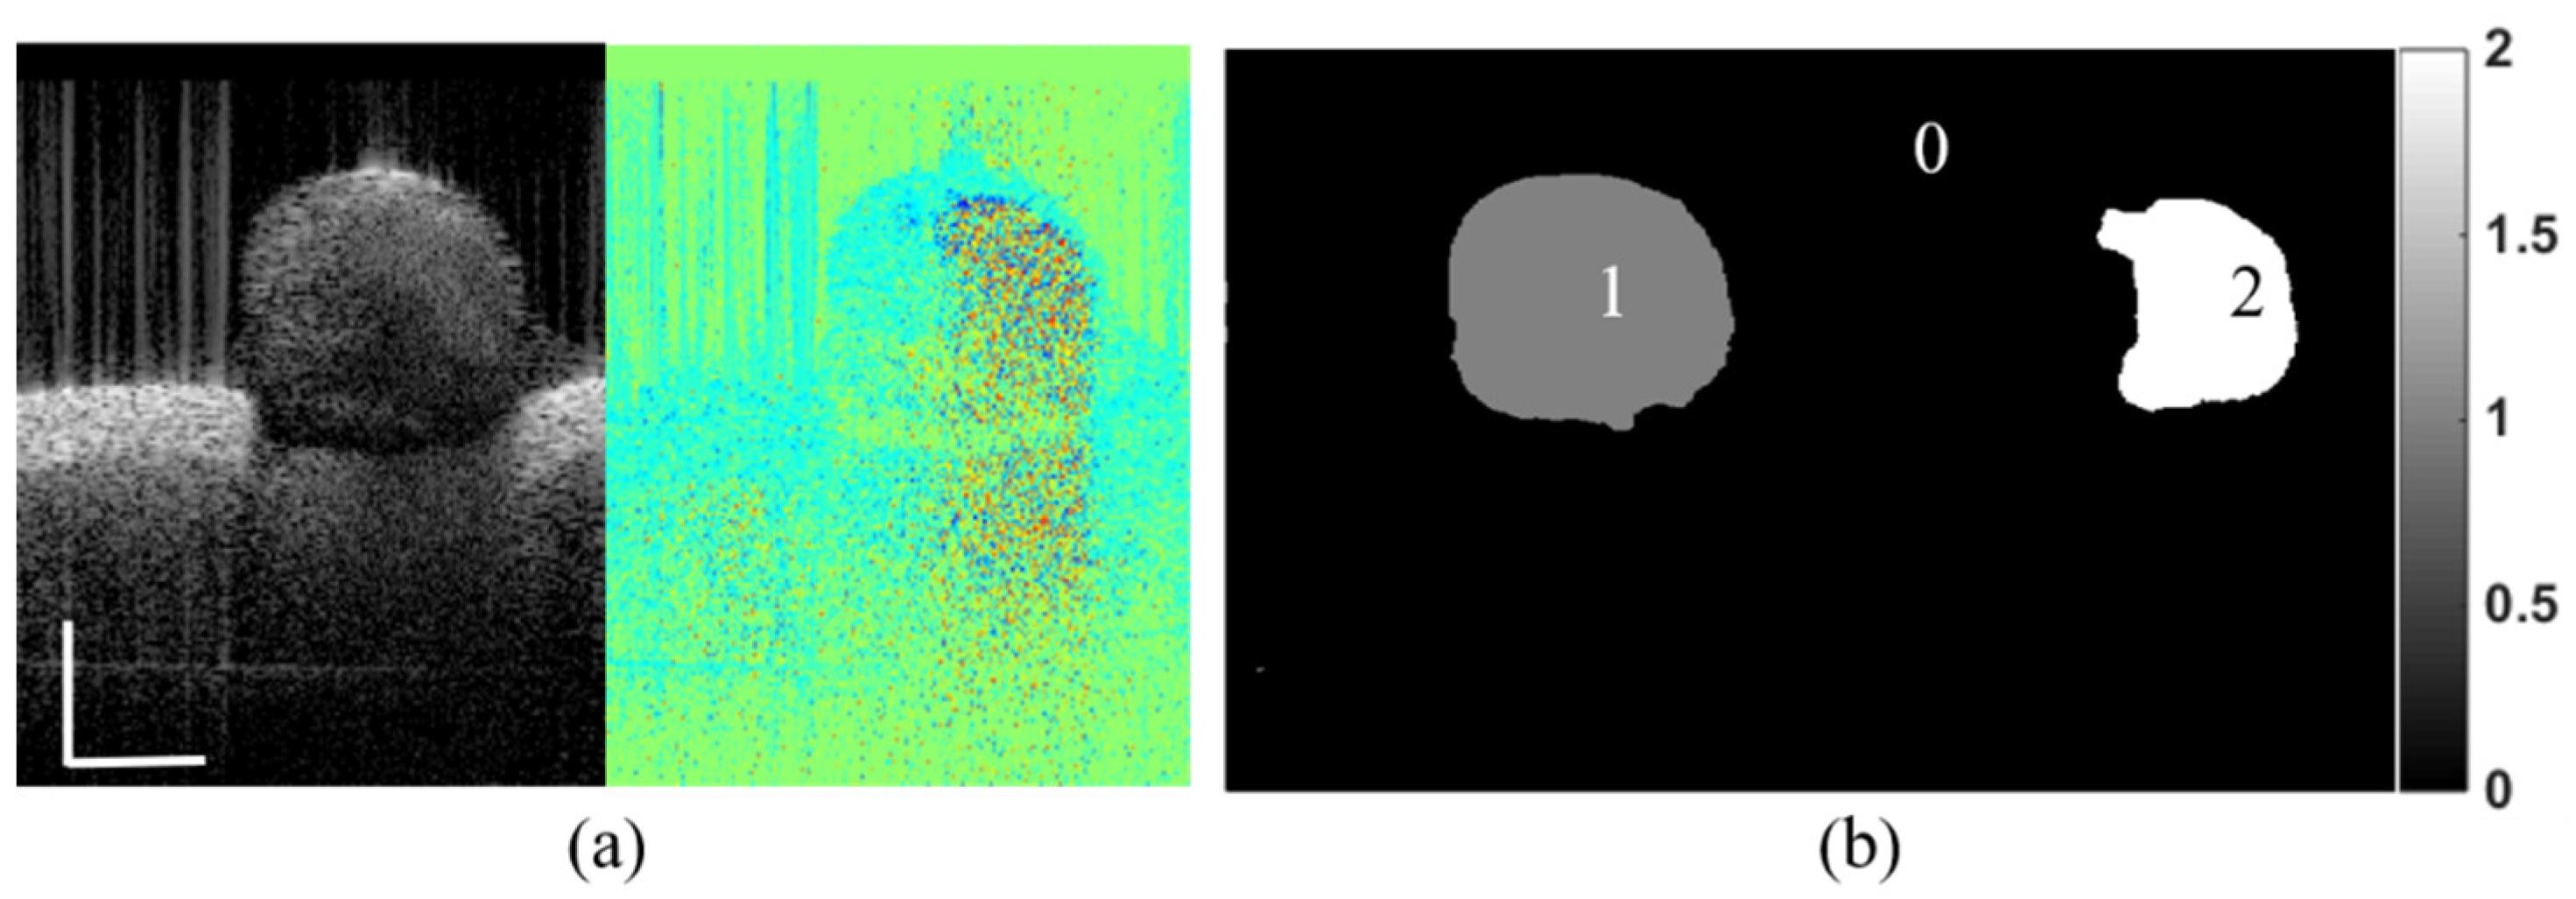

| Frame from Test Dataset | Random Walks | CU-Net | The proposed method | ||

|---|---|---|---|---|---|

| Intensity | Phase | Intensity | Phase | ||

| Dice | 0.966 | 0.945 | 0.954 | 0.948 | 0.967 |

| Time(s) | 19.08 | 19.03 | 0.31 | 0.37 | 0.63 |